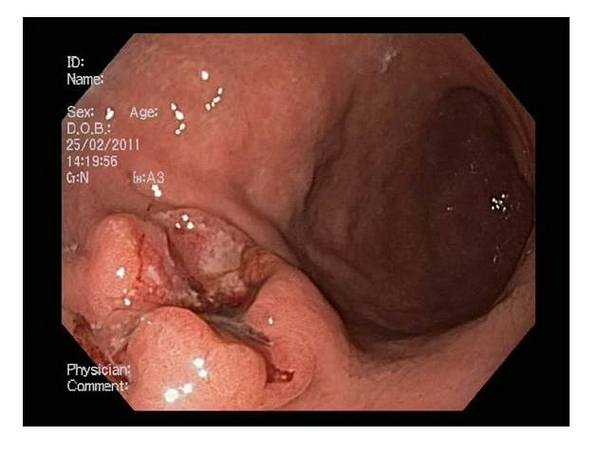

- эндоскопию;

При эндоскопии проводят биопсию (забор ткани для гистологии). Также делают лапароскопию и торакоскопию. Когда через минимальный разрез больному вводят микрокамеру, с помощью которой проводят осмотр брюшной или плевральной области.